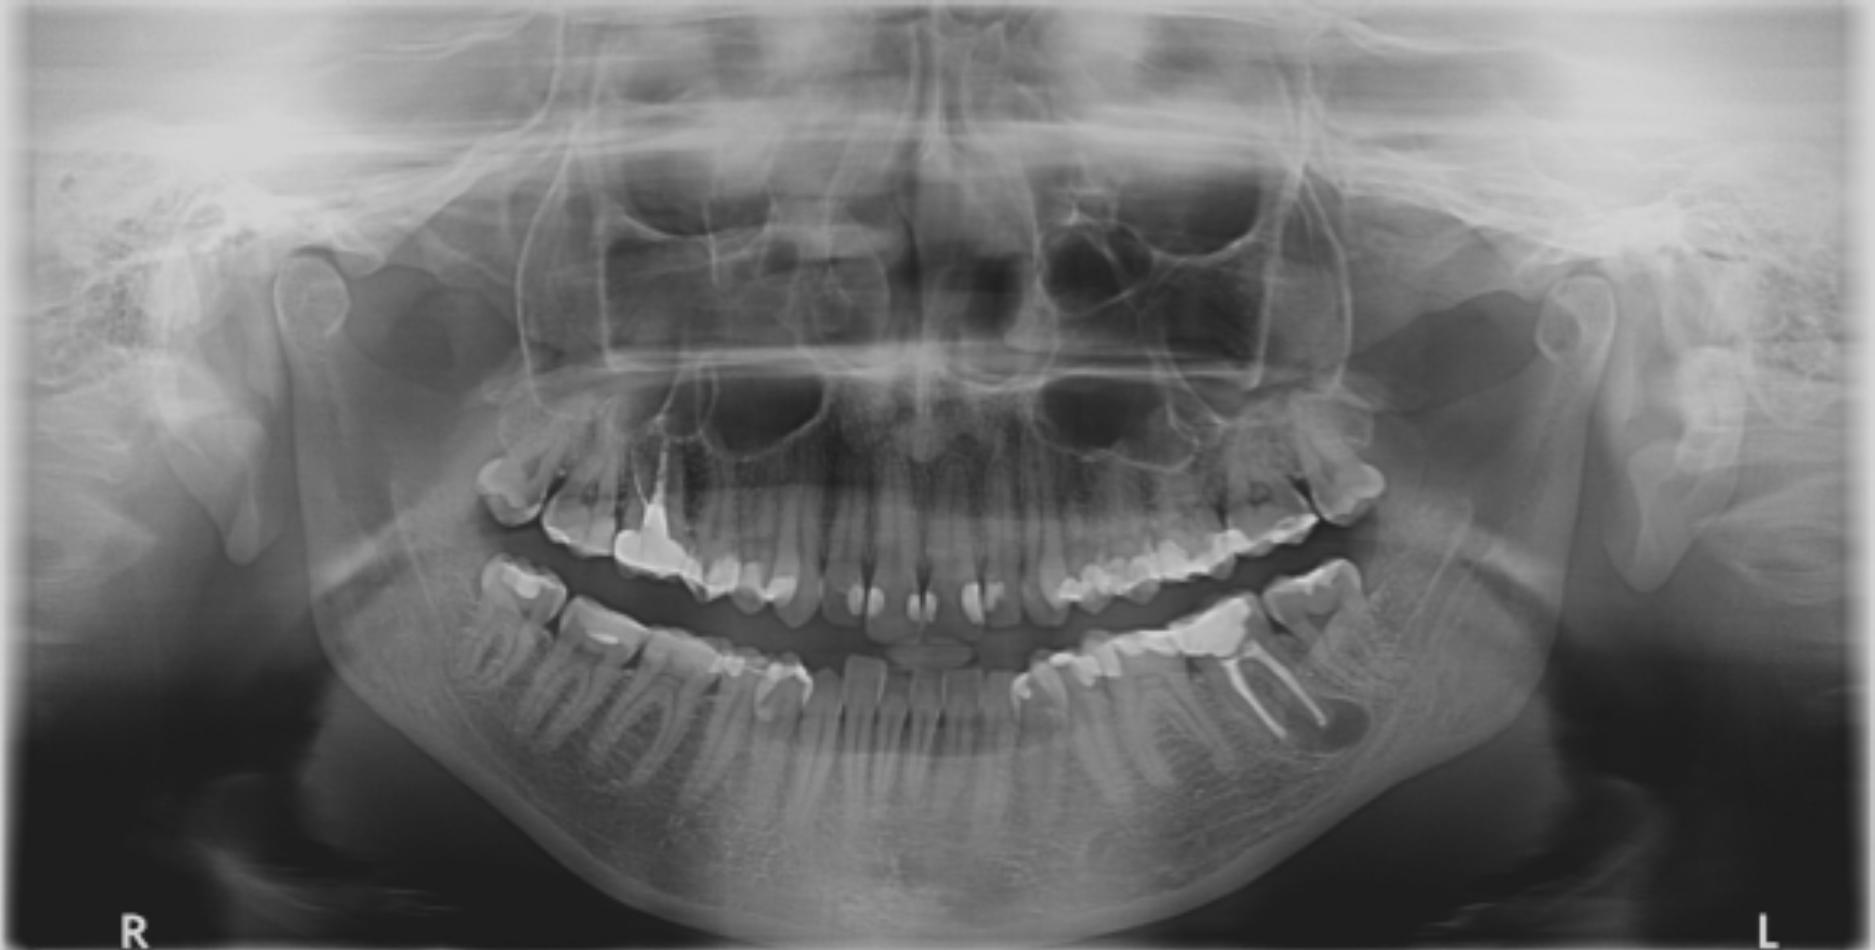

Po pewnym czasie ból powrócił – ząb zrobił się bolesny przy dotyku i nagryzaniu. Pacjentka wróciła do gabinetu, gdzie ponownie wykonano zdjęcie rentgenowskie, na którym przy wierzchołku korzenia dalszego była widoczna niewielka zmiana zapalna. Po przeprowadzeniu ponownego leczenia endodontycznego pacjentka nie odczuwała bólu przez kilka miesięcy, ale po pewnym czasie dolegliwości znowu powróciły. Ponieważ po wykonaniu zdjęcia pantomograficznego (ryc. 1) lekarz prowadzący doszedł do wniosku, że nie zna przyczyny problemu, pacjentka przyszła na konsultację do innego gabinetu. Po przeprowadzeniu wywiadu i badaniu wstępnym pobrano wyciski szczęki i żuchwy masą poliwinylosiloksanową w technice dwuwarstwowej w celu odlania modeli.

Ryc. 1. Widoczna zmiana zapalna na zdjęciu rentgenowskim przy wierzchołku korzeniu dalszym zęba 37.